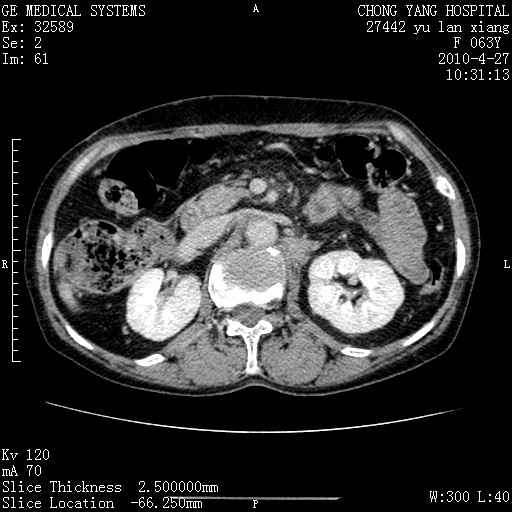

标题: CT26066:F63Y 上腹正中压痛半月,CA199:7400u/ml,MR示胰腺炎伴 [打印本页]

胰腺癌侵犯腹腔动脉干-分支、胃壁、左侧膈肌伴胰周及腹膜后淋巴结转移、胆囊切除术后。

胰腺癌侵犯腹腔动脉干-分支、胃壁、左侧膈肌伴胰周及腹膜后淋巴结转移、胆囊未显影。